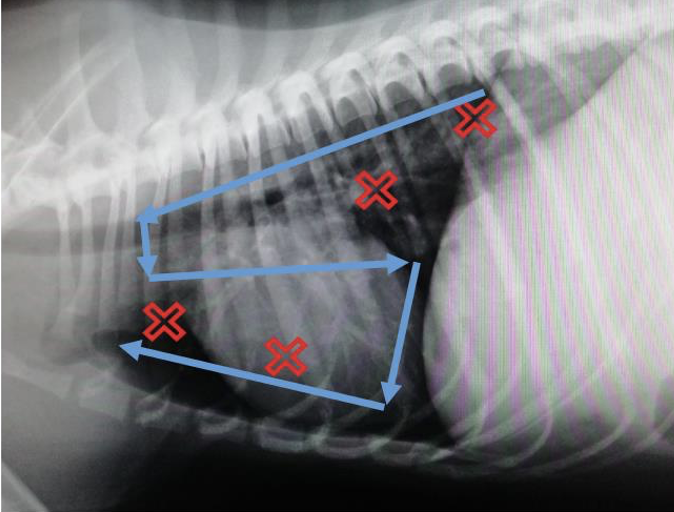

What is VetBLUE?

A

Veterinary bedside lung ultrasound exam

Allows assessment of lung parenchyma & pleural space

4 point scan on both sides of chest (red X’s)

13

Q

What is PLUS?

Pleural lung ultrasound

Addition to VetBLUE

sweep ‘S’ across lung fields (blue lines)

9 points in total on both sides of chest